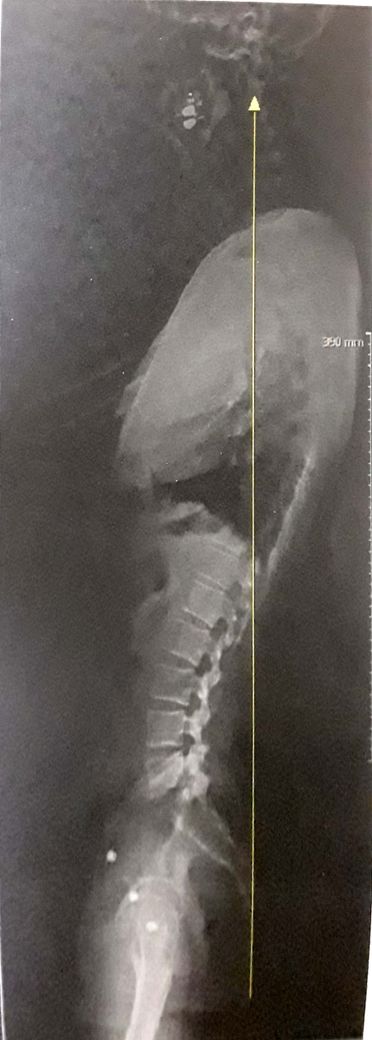

일자목 일자등 확인 부탁드립니다.

일자목 일자등 인 것 같은데 맞나요?

거북목과 일자목 재활 운동 방법이 다르다고 해서 확인 부탁드립니다.

• 1번 째 사진